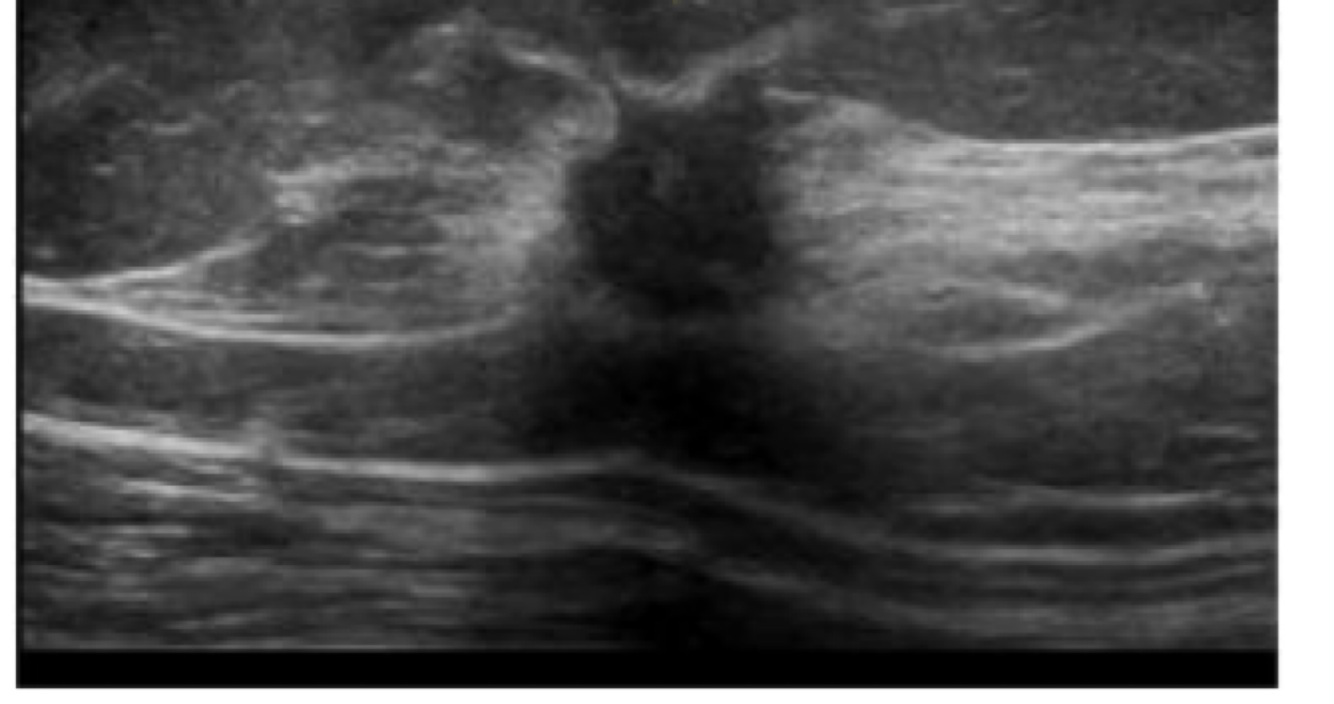

What kind of cyst is this?

Simple cyst (breast in this image)